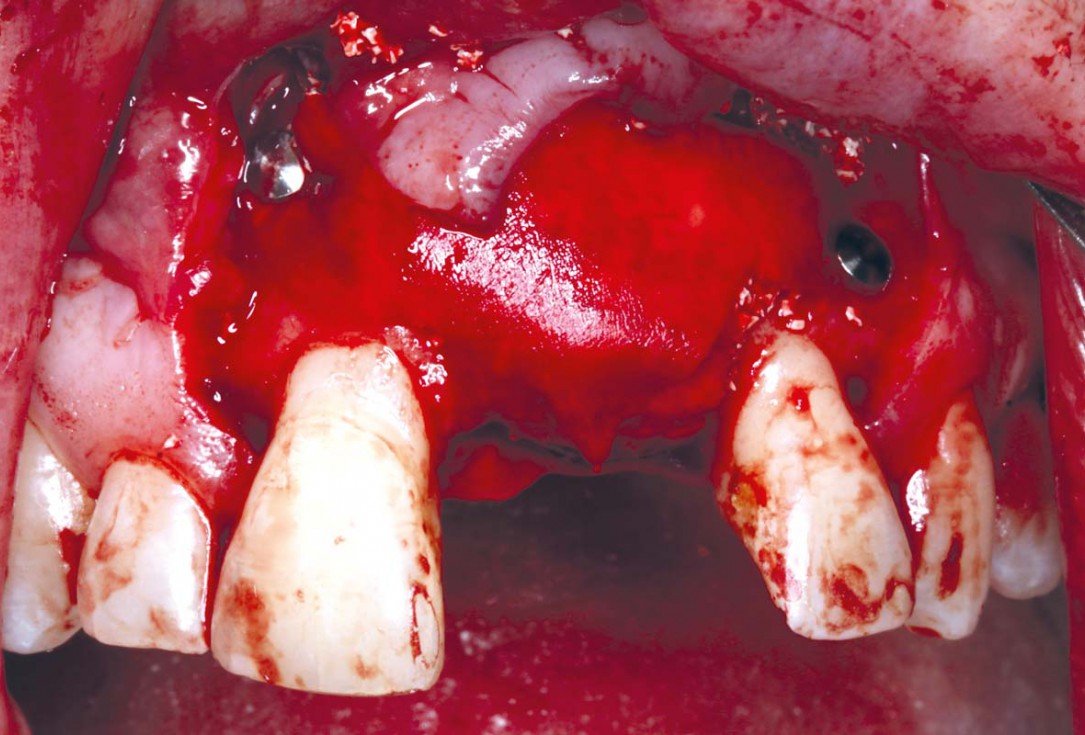

5/35 - Three-sided full thickness flap and cleaning the surgical area from the granulation tissueBlock grafting in the aesthetic zone with maxgraft®, Jason® membrane and cerabone® - Dres. H. Maghaireh and V. Ivancheva

6/35 - Three-sided full thickness flap and cleaning the surgical area from the granulation tissueBlock grafting in the aesthetic zone with maxgraft®, Jason® membrane and cerabone® - Dres. H. Maghaireh and V. Ivancheva